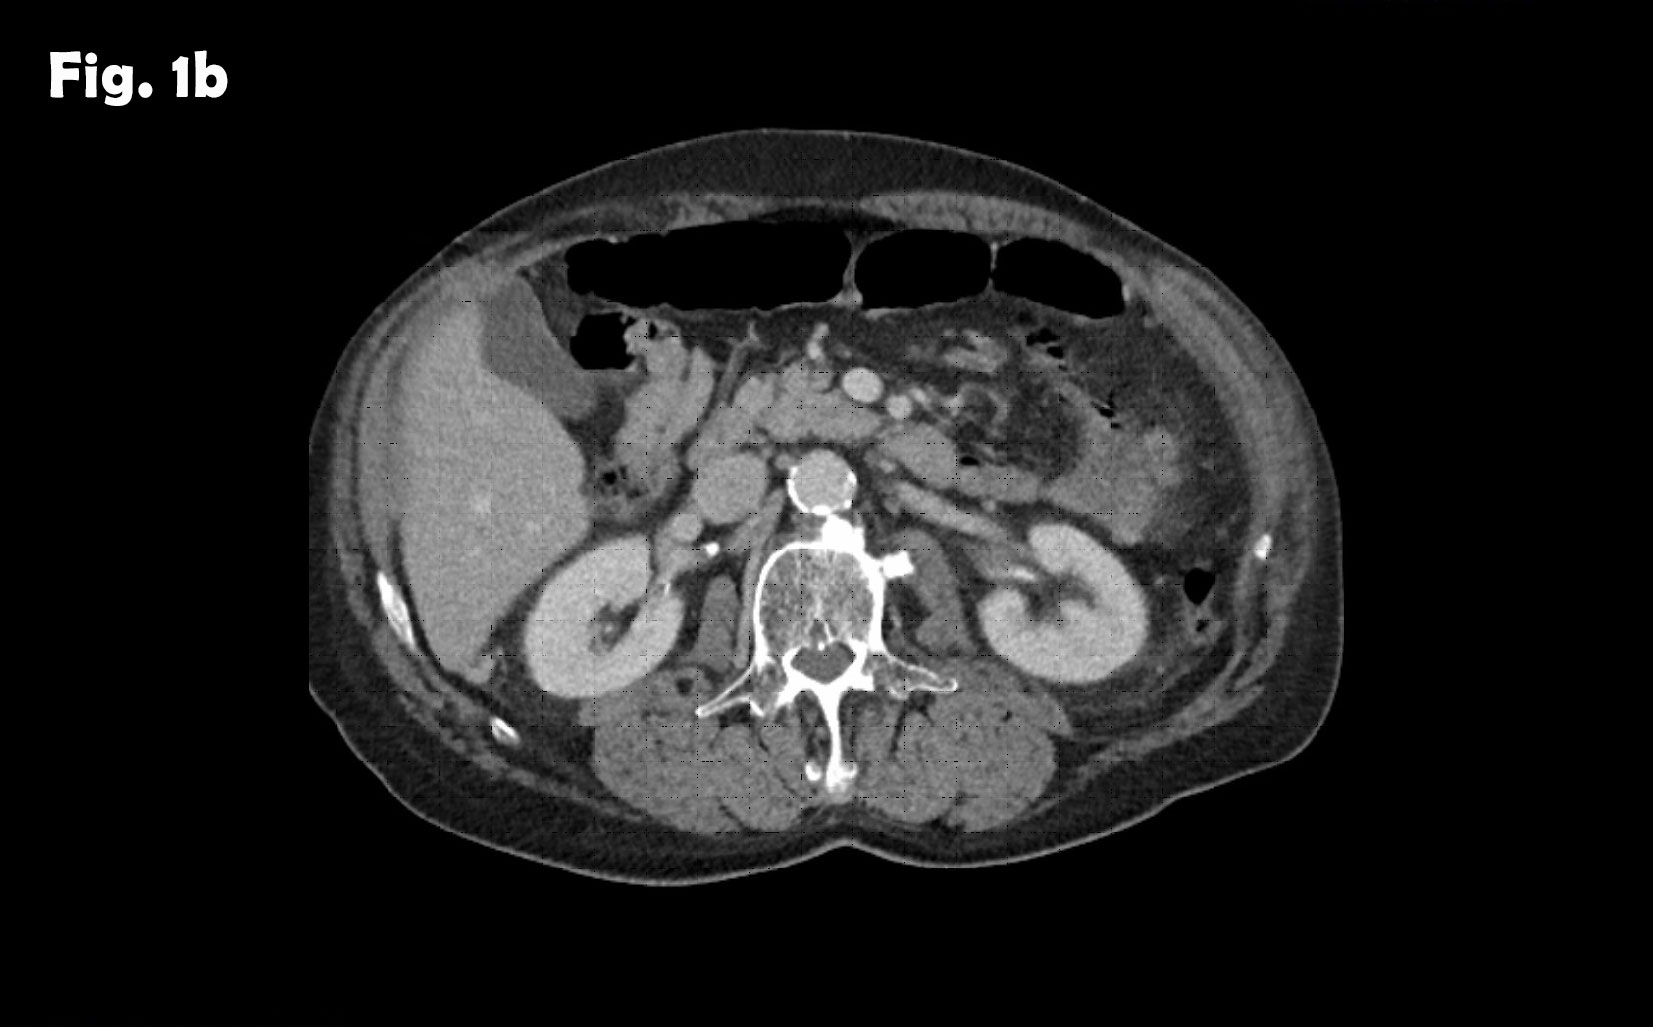

Computed tomography of the abdomen demonstrated no spleen and numerous small nodules of up to 28 mm between intestinal loops and between the liver and diaphragm suggesting a disseminated neoplastic process, thought to be most probably, peritoneal carcinomatosis. The arrow on the scan illustrates the lesion that was biopsied which excluded neoplasia and demonstrated splenic tissue.

Figure 4: At different abdominal locations more echogenic round oval lesions upt to 30 mm were identified by ultrasound. The lesions were best depicted during the late phase enhancement behind the accessory spleen next to the lesion shown in figure 2 (a) and elsewhere in the abdomen (b). The Figure 3c represents the CT finding shown in figure 1.